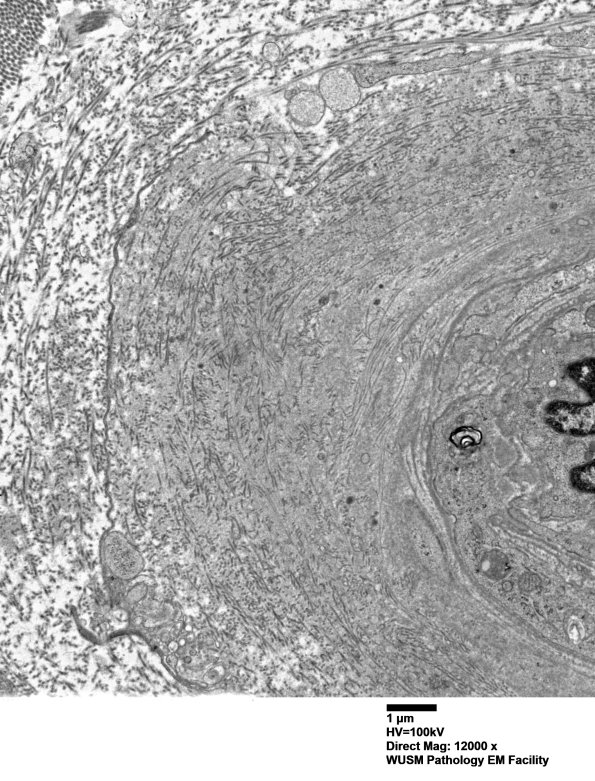

Washington University Experience | VASCULAR | Hypoxia-Ischemia, fetal-neonatal | White Matter | 14B1B (Case 14) EM004 - Copy

14B1B (Case 14) EM004 - Copy